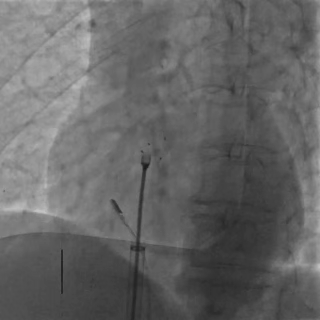

DSA下左盘展开,轻轻牵拉成型线辅助左盘成型,左盘1个Mark点靠近腰部2个Mark点

后撤钢缆和鞘管使左盘贴靠房间隔

后撤鞘管,展开右盘面,DSA下可见右盘1个Mark点靠近左盘和腰部3个Mark点